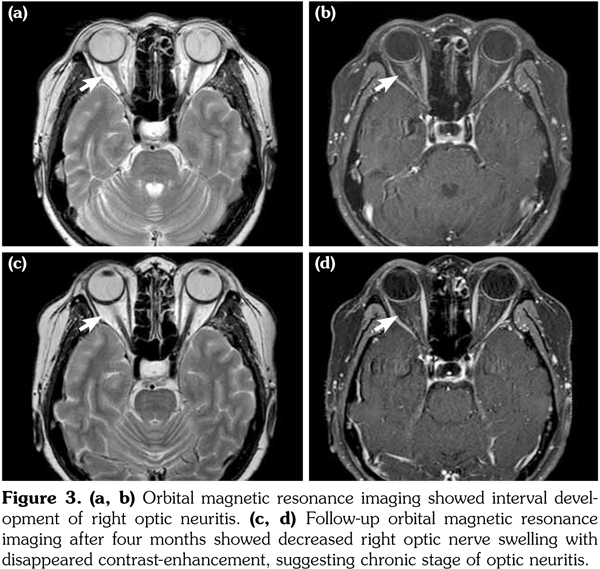

Two weeks after the third cycle of intravenous cyclophosphamide and a reduction of prednisolone to 20 mg, the patient visited the emergency room with a severe headache. However, brain MRI showed no new lesions, only chronic- stage encephalitis with atrophic changes in the previously observed multiple edematous lesions. Two days later, she complained of right-eye pain with a sudden decrease in right visual acuity. Ophthalmological examinations showed a right relative afferent pupillary defect, decreased right visual field, and mild swelling of the right optic disc. Orbital MRI showed interval development of right optic neuritis (Figure 3a, b). Whole-spine MRI showed no evidence of myelitis in the spinal cord. Steroid pulse therapy was administered for three days and plasmapheresis was performed five times. Her vision improved enough for her to read large letters. Results of tests for the anti- AQP4 antibody were positive, and the patient was diagnosed with NMOSD related to pSS. Follow-up orbital MRI after four months showed decreased right optic nerve swelling with disappeared contrast-enhancement, suggesting chronic stage of optic neuritis (Figure 3c, d).